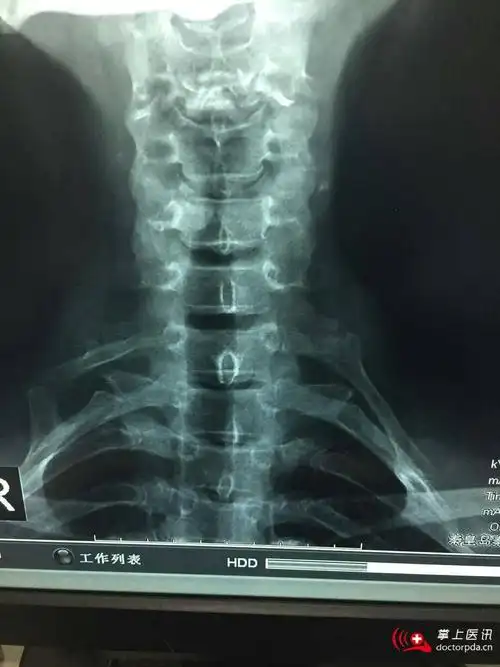

颈肋

70岁.很典型的颈肋.

颈肋,c7横突过长,第1肋骨形态异常,锁骨或第1肋骨骨折畸形愈合,肩锁

图10-10 胸廓出口的解剖图10-11 第七颈椎形成的颈肋可以压迫臂丛神经